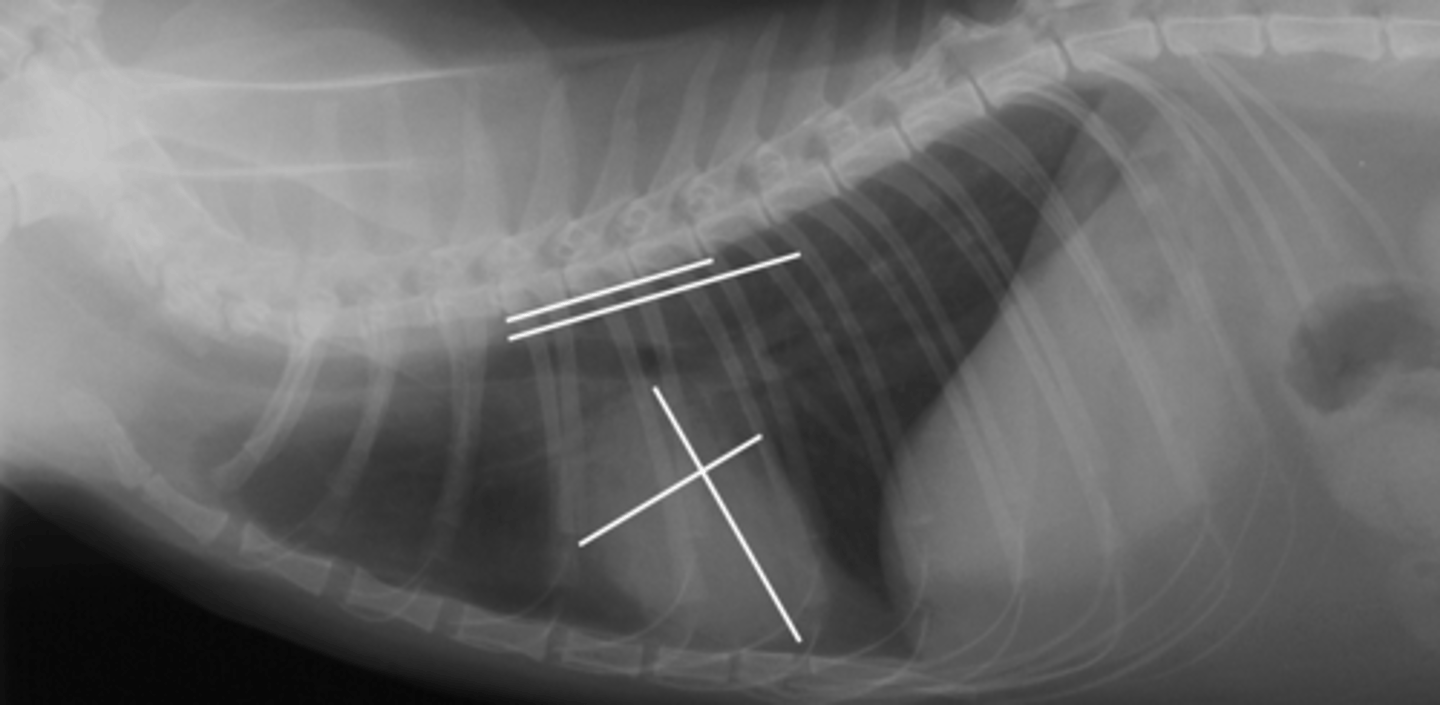

3.1 +4.2 =7.3

(Fel - 8)

Given the following radiograph do we have an enlarged heart?